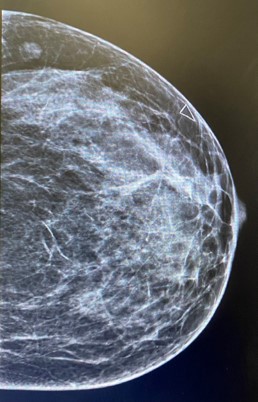

Left breast and axilla ultrasound and Mammogram showed: Left breast palpable lesion with architectural distortion in the upper lateral mid/anterior third at 3:00, It measures 0.9 cm and seen with no significant vascularity. A clip was placed.

Figure 2: Left mammographic views CC of the left breast showing an irregular, spiculated, high-density mass in the upper outer quadrant. The lesion causes architectural distortion without associated calcifications. Findings are consistent with desmoid-type fibromatosis confirmed on histology.

Mammography presents irregular walled and highly dense lesion with no calcifications mimicking sometimes breast carcinoma [6].

Radiologic evaluation of our case revealed soft tissue mass inducing architectural distortion.